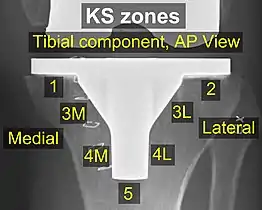

Components and zones

Standardized zones around the components are used for specifying for example signs of loosening on radiographic follow-up. There are various classification systems for specifying such zones,[42][43] including by KS (Knee Society) zones published in 2015.[41]

Main components of a knee prosthesis. KS zones, anteroposterior (AP) view.[41]

KS zones, anteroposterior (AP) view.[41]

Specific KS zones are as follows, with * meaning that the zone can be specified as "A" (anterior), "P" (posterior), "M" (medial) or "L" (lateral):[41]

- Tibial component:

- Zone 1: Anterior on lateral view, medial on anteroposterior (AP) view.

- Zone 2: Posterior on lateral view, lateral on AP view.

- Zone 3: Central keel/stem/peg fixation region*

- Zone 4: Stem extension*

- Zone 5: Inferior aspect of keel or stem